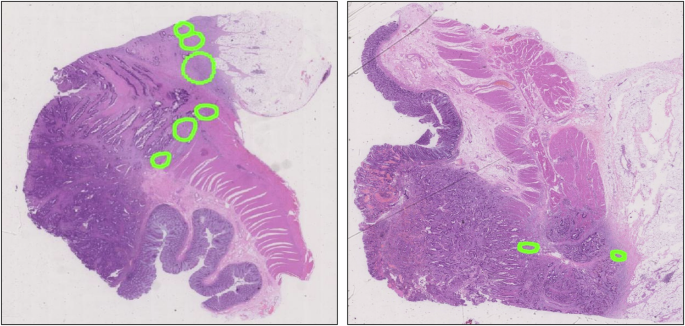

Quantitative analysis of TB annotations in tumor invasive front patches

In the evaluation of TB annotations in tumor invasive front patches, the TBAM-TIFP demonstrated variability and adaptability in its annotation capabilities across multiple datasets. As illustrated in Fig. 8, the model’s predictions were compared with consensus annotations from three pathologists on each dataset. In the PUTH-IV patch, the TBAM-TIFP annotated 3 TBs, matching exactly the manual annotations of 3 TBs by pathologists, with no missed annotations, indicating its high accuracy and reliability on this dataset. However, in patches from the TCGA-COAD-EV and TCGA-READ-EV, the annotation performance exhibited significant deviations from expert annotations. In the TCGA-COAD-EV patch, the model annotated 9 TBs, whereas the pathologists identified 13 TBs, resulting in several missed annotations. This was likely due to the irregular shapes and small sizes of some TBs, suggesting that the model is more prone to misclassifying challenging TBs as background in the presence of diverse sample characteristics and background noise. Similarly, in the TCGA-READ-EV patch, the TBAM-TIFP annotated 5 TBs, compared to 7 TBs annotated by the pathologists, again indicating missed annotations. These discrepancies further underscored the impact of inter-dataset variability, including differences in staining protocols and tissue morphology, on model performance. The observed missed annotations appeared closely related to the diversity and complexity of WSIs. Overall, while the TBAM-TIFP showed its better TB annotation performance on the PUTH-IV dataset, the observed gaps on external validation datasets highlighted the need for further model optimization to improve robustness against varying sample features and background noises. In particular, enhancing the diversity of the training dataset might help improve the model’s flexibility and annotation accuracy in complex tumor microenvironments.

A Effect comparison of TB annotations in a patch from the PUTH-IV. B Effect comparison of TB annotations in a patch from the TCGA-COAD-EV. C Effect comparison of TB annotations in a patch from the TCGA-READ-EV.